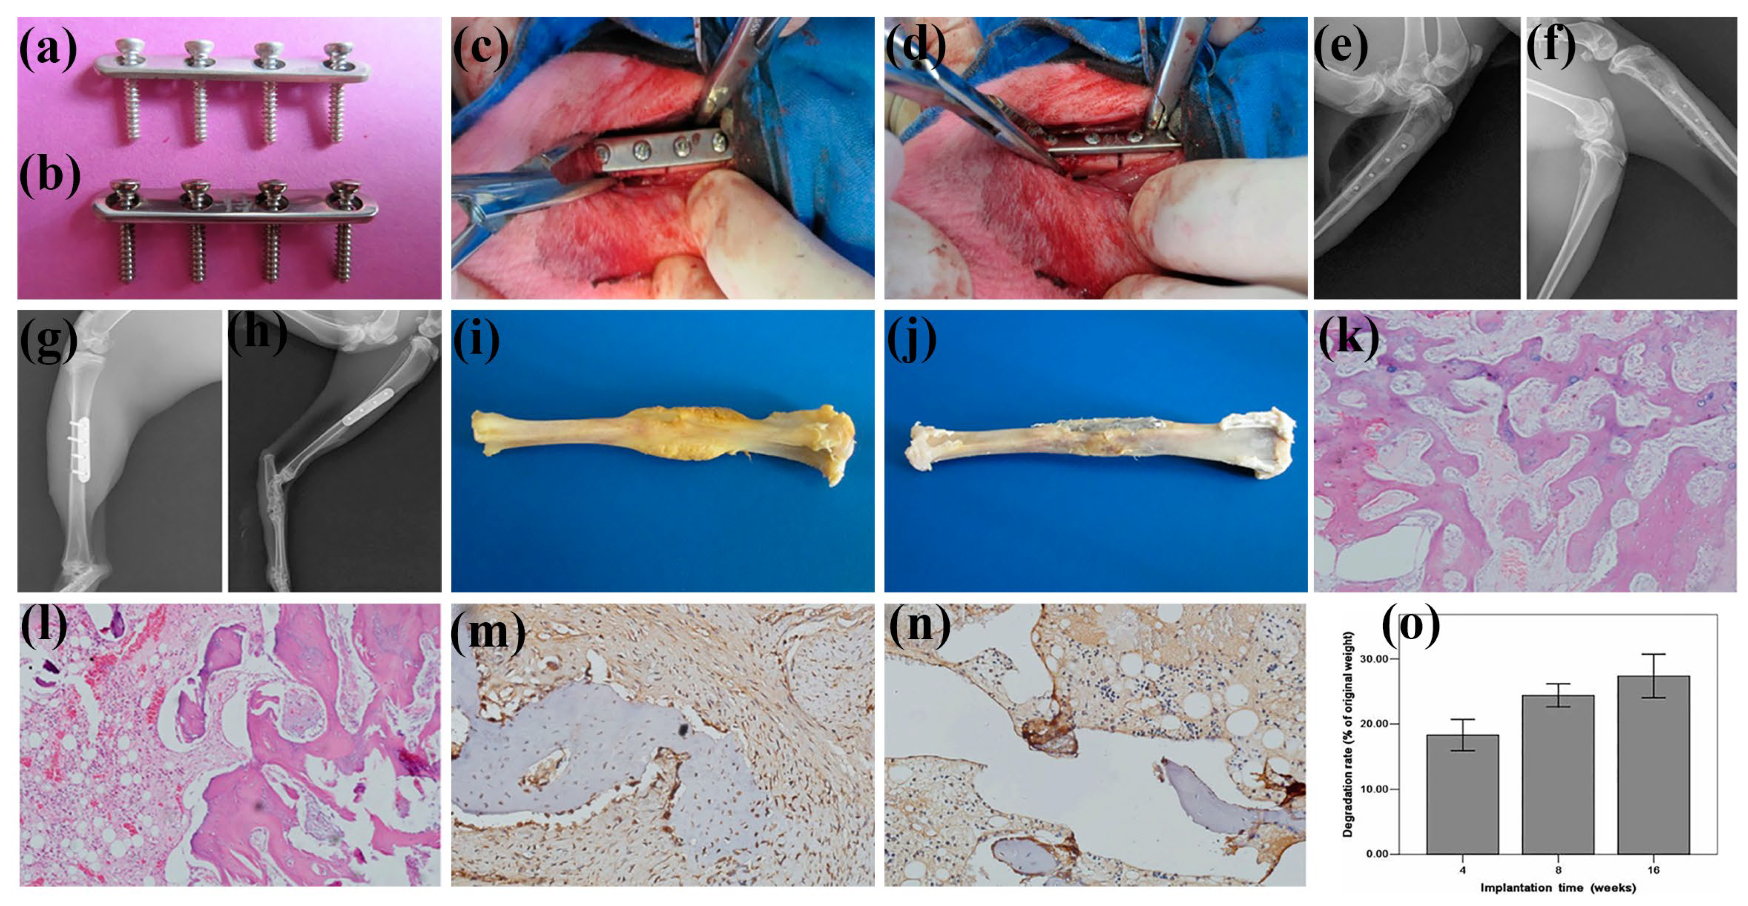

3.3. Bone Plate

- Wang, Y.; Liang, W.; Liu, X.; Li, Q.; Xie, Y.; Jiang, Y. Osteogenesis and degradation behavior of magnesium alloy plate in vivo. Eur. J. Inflamm. 2021, 19, 20587392211034078. [Google Scholar] [CrossRef]